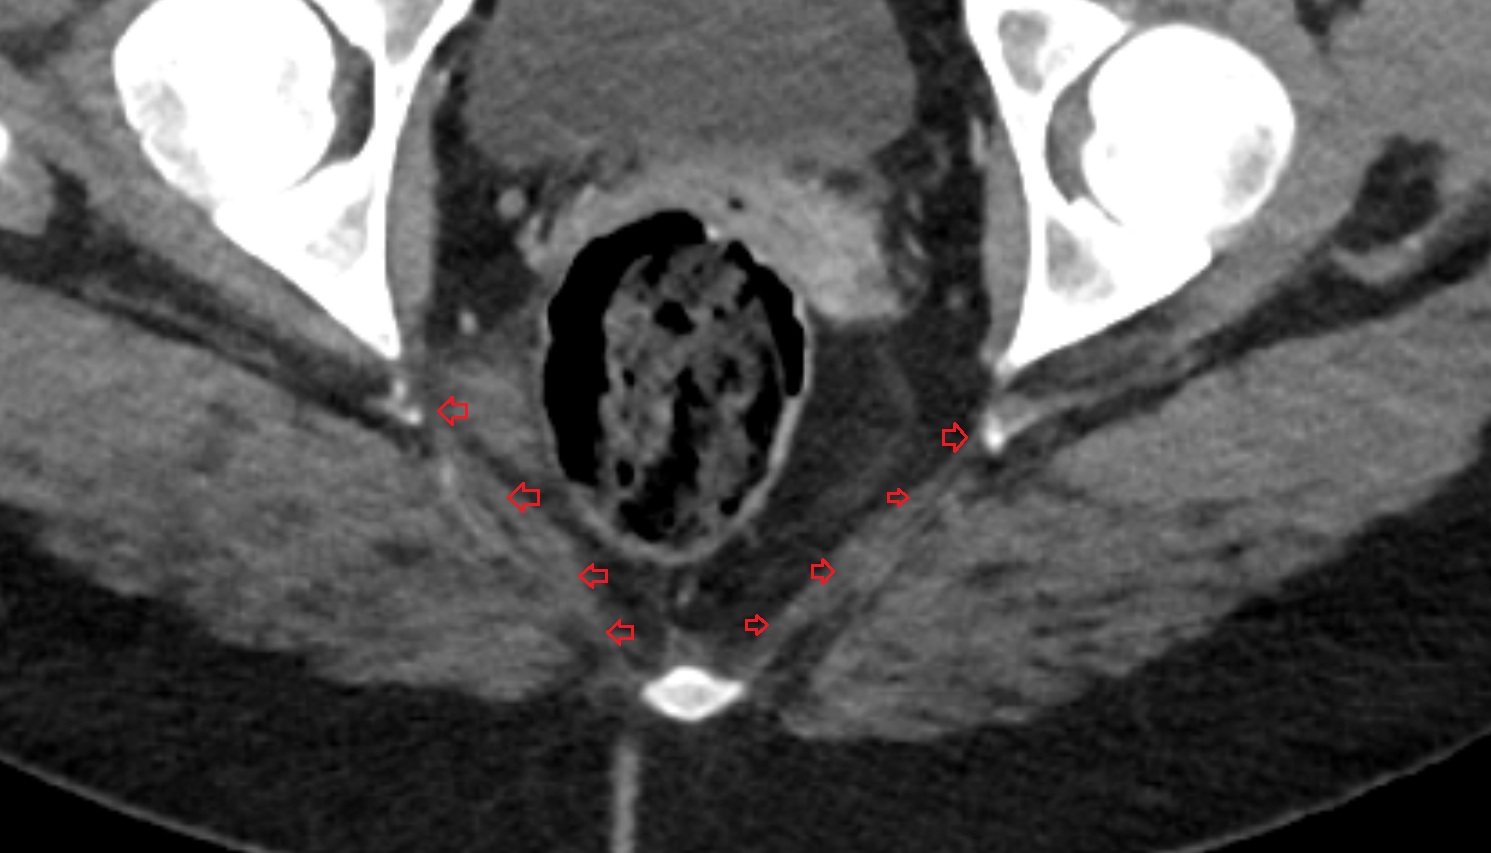

- Mesorectal fascia

- Mesorectum

- Rectum

- Mesorectal free fluid